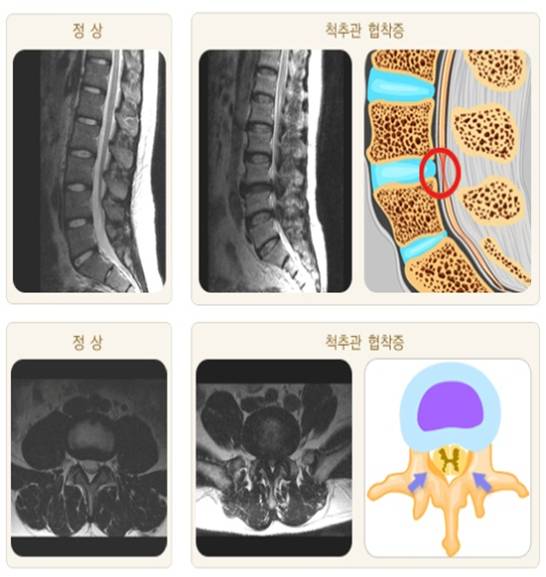

- 척추관협착증: 척추관이 좁아져 신경을 압박하는 상태로, 주로 노화로 인한 퇴행성 변화나 후종인대골화증, 외상 등에 의해 발생합니다. 척추관협착증은 주로 허리나 목 부위에서 발생하며, 신경 압박으로 인해 다양한 증상을 유발할 수 있습니다.

척추관협착증 증상

척추관협착증의 주요 증상은 다음과 같습니다.

- 요통: 허리 부위에서 나타나는 통증으로, 장시간 서 있거나 걸을 때 더욱 심해질 수 있습니다.

- 방사통: 허리에서 다리로 이어지는 방사통이 나타날 수 있습니다.

- 무감각 및 저림: 다리나 발에 무감각이나 저림 증상이 나타날 수 있습니다.

- 근력 약화: 다리나 발의 근력이 약해질 수 있습니다.

- 운동 기능 장애: 걷는 것이 어렵거나 균형을 잡는 데 어려움을 겪을 수 있습니다.

- 배변 및 배뇨 장애: 심한 척추관협착증은 배변 및 배뇨 기능에 영향을 미칠 수 있습니다.